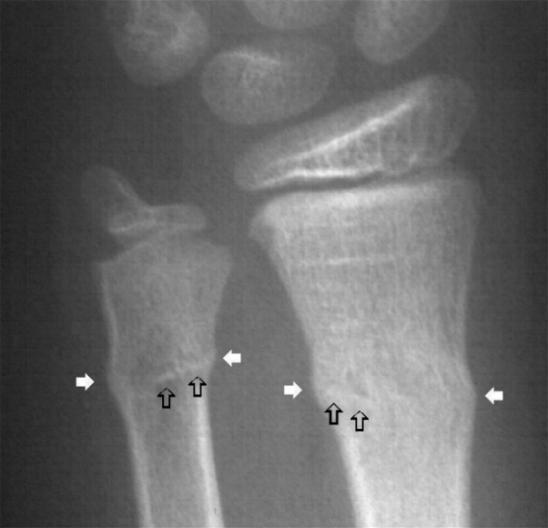

Greenstick fracture

concave side

Torus Fracture